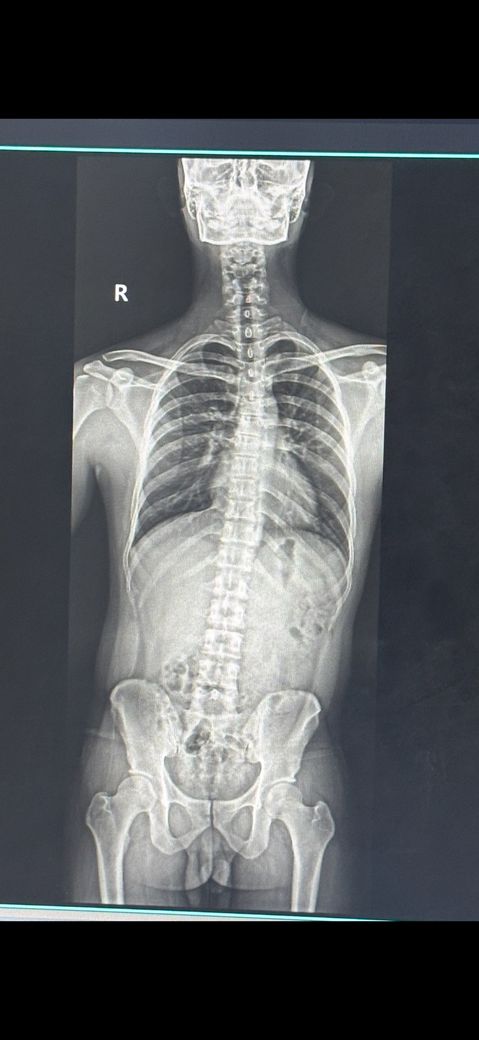

척추 골반 교정 이정도 휘어도 가능할까요!

어제 일하다가 허리 삐끗해서 병원에 엑스레이 찍어봤는데 이러네요… 척추 교정 센터 다시 다닐려고 합니다 풋살이나 달리기를 주로 하는데 균형이 안 맞아서 그런지 계속 발목삐고 붓더라구요 이정도 휜것고 교정 가능할까요….?

사진상으로보기에는 틀어진골반을 보상하기위해서 상체가 한쪽으로 쏠려있는것으로보입니다 도수치료를통해서 몸의 불균형을 교정하고 필요한 운동들을 배워 꾸준하게 한다면 더 증상이 심해지지않도록 막을수있으니 따라해보시길 바랍니다

X-ray상 "구조적 측만 + 골반 비대칭"이 함께 보이는 유형으로, 뼈 자체를 완전히 펴는 건 어렵습니다.

다만 "기능적 틀어짐(골반.근육 불균형)"은 재활운동.물리치료로 "통증.균형.발목 삐는 빈도는 충분히 개선" 가능합니다.

x-ray로 보아서는 골반 틀어짐과 척추측만증, 신체 전반적인 중심이 무너져 있으신 것으로 보입니다.